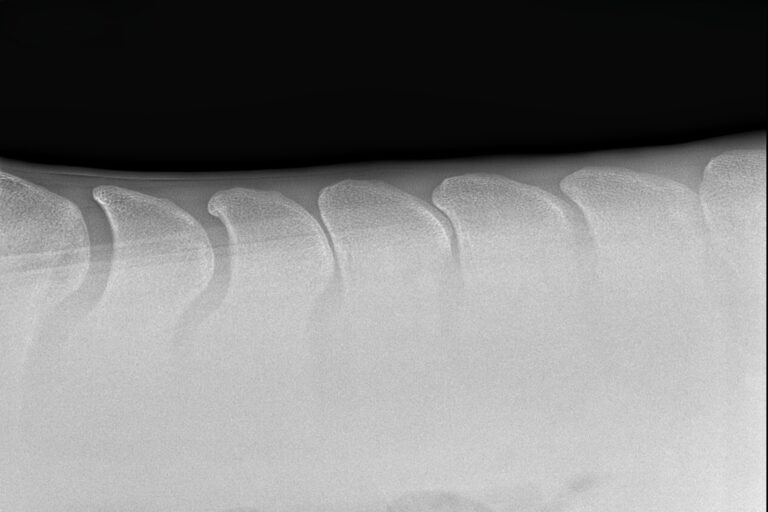

Kissing spine u koni to schorzenie grzbietu prowadzące do bólu i kulawizny. Dowiedz się, jak rozpoznać objawy i na czym polega leczenie choroby Baastrupa.